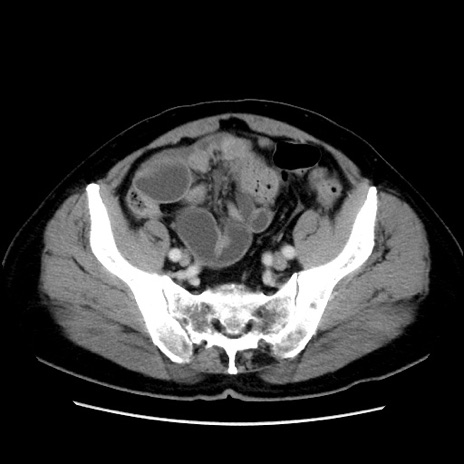

症例16(横断像)

【症例】 70歳代男性

【主訴】 腹痛、嘔吐

【現病歴】 約1ヶ月前より間欠的に腹痛と嘔吐あり、当院消化器内科を受診したところCTで多発する肝臓のLDAを指摘され、精査中であった。以降は消化器症状は安定していたが、2日前より嘔気と腹痛があり、同日より排便・排ガスが消失した。改善認めず、 本日、救急外来を受診した。

【既往歴】 大腸ポリープ切除後。

【身体所見】意識清明・会話良好、BT 36.3℃、BP 127/80mmHg、 P 80bpm、腹部:膨満あり、平坦・軟、上腹部正中および下腹部正中に圧痛あり、反跳痛なし、筋性防御なし。

【データ】WBC 7200、CRP 0.77